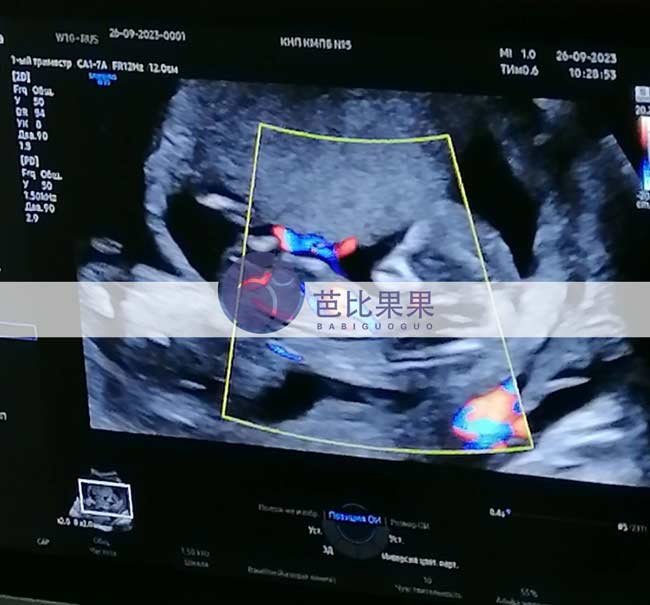

J女士家的乌克兰试管妈妈来做孕12周B超产检,胎宝宝已经在胎稳了,祝愿接下来一路顺利到出生

J女士家的乌克兰试管妈妈来做孕12周B超产检,胎宝宝已经在胎稳了,祝愿接下来一路顺利到出生